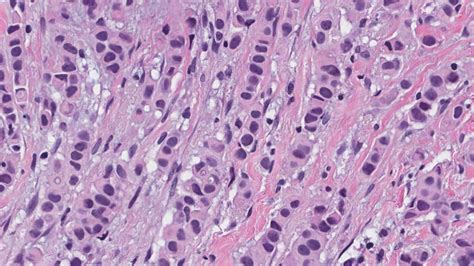

Alright guys, let's break down what metastatic invasive breast carcinoma truly means. So, you've heard about invasive breast cancer, right? That's when the cancer cells have gone rogue, escaping the confines of the milk ducts or lobules where they originated and started invading the surrounding breast tissue. Think of it like a tiny, unwelcome guest that has decided to break down the walls and explore the neighborhood. But the real kicker, the part that elevates it to metastatic , is when these adventurous, and frankly dangerous, cells decide to go on a world tour of your body. They detach from the primary tumor, hop onto the highway of your bloodstream or lymphatic system, and travel to distant lands – organs like the bones, lungs, liver, or brain. These new colonies of cancer cells are called metastases. So, metastatic invasive breast carcinoma is essentially invasive breast cancer that has spread to these other parts of the body. It's also known as Stage IV breast cancer, and it’s the most advanced stage. It's important to understand that even when the cancer spreads, the metastatic cells are still considered breast cancer cells. For example, if breast cancer spreads to the lungs, it's called metastatic breast cancer in the lungs, not lung cancer. This distinction is crucial because the treatment is usually based on the original cancer type. The development of metastasis is a complex biological process. It involves several steps: primary tumor growth, invasion into surrounding tissues, intravasation (entering blood or lymph vessels), survival in circulation, extravasation (exiting vessels at a distant site), and finally, the formation of a new tumor, known as a metastatic lesion. Each step presents hurdles for the cancer cells, but when they succeed, it leads to the challenging reality of Stage IV disease. Understanding this process helps us appreciate why treatments often need to be systemic, targeting cancer cells wherever they might be hiding.